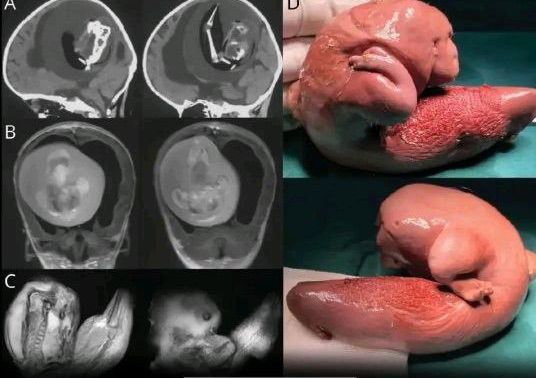

A rare and unusual case was reported in China, where doctors surgically removed a malformed twin from the brain of a 1-year-old girl. The little girl had shown signs of developmental delays and had an unusually large head, leading to the discovery. The mass was actually a partially formed twin, with bones like a spine, arms, and even finger-like buds. This rare condition, known as fetus-in-fetu, happens in about 1 in 500,000 births, where one twin grows inside the other. Fetus-in-fetu is often mistaken for a type of tumor, but it can be identified by the presence of actual body parts. While most cases involve the mass growing in the abdomen, it's incredibly rare for it to be found in the brain. Fewer than 200 cases have been documented worldwide, and this adds to the small number of cases where the twin developed in such an unusual location.